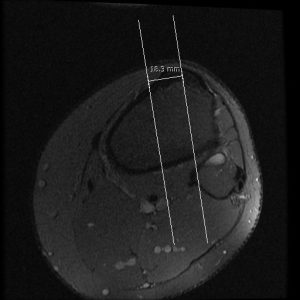

Tibial Tubercle to Trochlear Groove Distance Measured by Posterior ...